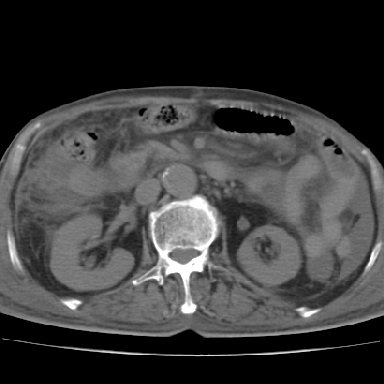

以下是引用qian在2006-12-4 19:11:00的发言:[br]胸腔和腹腔内均见有液性影,肝上极包膜下有一较大椭圆形低密度影,密度均匀,边缘清晰,结合病史考虑术后肝脓肿并胸腹腔积液。

以下是引用chry3在2006-12-4 21:05:00的发言:[br]应该往上扫几层,我考虑膈下脓肿。[br]大家考虑:胃部手术怎会造成肝内脓肿,隔下脓肿到是会造成的

以下是引用dyqct在2006-12-4 19:54:00的发言:[br]考虑:1、肝包膜下脓肿;[br] 2、少量腹水;[br] 3、右侧少量胸膜腔积液。